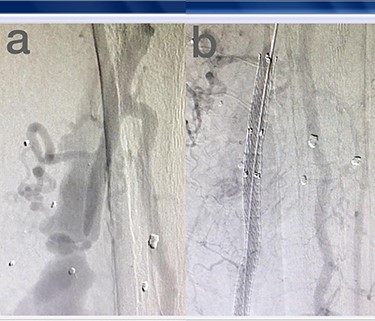

Sites of injury included 6 Posterior Tibialis arteries (27.2%) (Fig. 1), 2 deep femoral arteries (9.09%), 2 Superficial femoral arteries (9.09%) and 2 maxillary arteries (9.09%). We had only one injured artery (4.54%) in each of the following sites: internal pudendal a., Axillary a. (Fig. 2), Proneal a., Lumbar a., External carotid a., Anterior Tibialis a., common iliac a. (Fig. 3), temporal a., Thoracic aorta and Internal iliac artery (Fig. 4).

(a) Internal iliac artery before intervention, (b and c) after coil embolization.